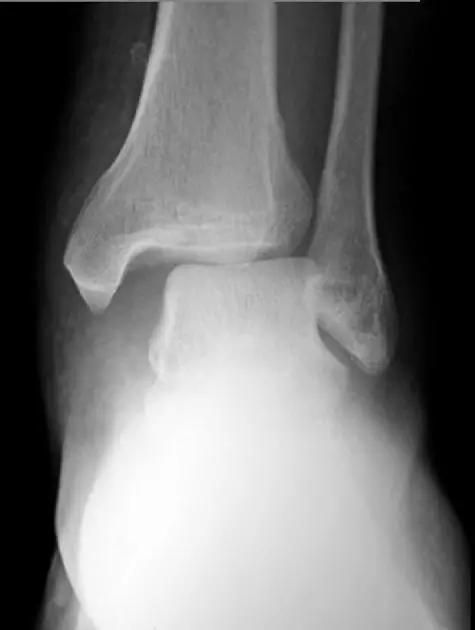

10. Cotton 骨折

是指伴有双踝及后踝的三踝骨折。